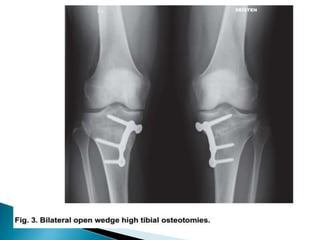

Four basic types are most commonly used

 medial opening wedge,

 Wedge bone graft and rigid fixation required.

Opening wedge osteotomy .